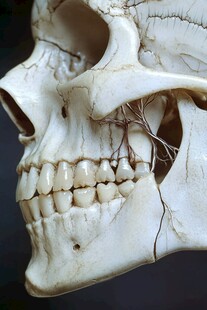

左下颌骨 非商作品

左下颌骨 非商作品 -

人体解剖学 共享分: 80

人体解剖学 共享分: 80 -

头骨化石标本 共享分: 30

头骨化石标本 共享分: 30 -